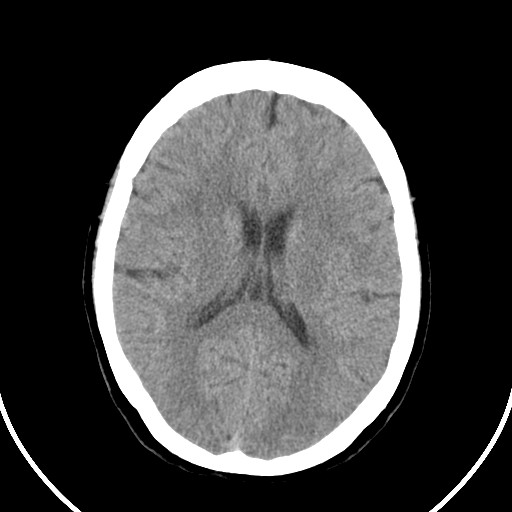

标题: CT21850:女,56岁,右中指淤肿,右手麻痹1天

女,56岁,右中指淤肿,右手麻痹1天

右侧侧脑室旁脑白质腔隙性脑梗死。

右侧基底节多发小梗塞

作者: huangyinshan    时间: 2009-8-25 15:37

右基底结区腔梗

右侧基底节区腔隙性脑梗塞

右侧基底节多发腔梗!

双侧侧脑室额角旁对称性略低密度影,边缘模糊,无占位效应,考虑轻度脑白质稀疏症(病人有高血压吗).,右枕叶低密度影多为伪影,不放心薄扫一下.

考虑脑白质病。

考虑脑白质病

右枕叶条状低密度影不应该忽略可能极具意义